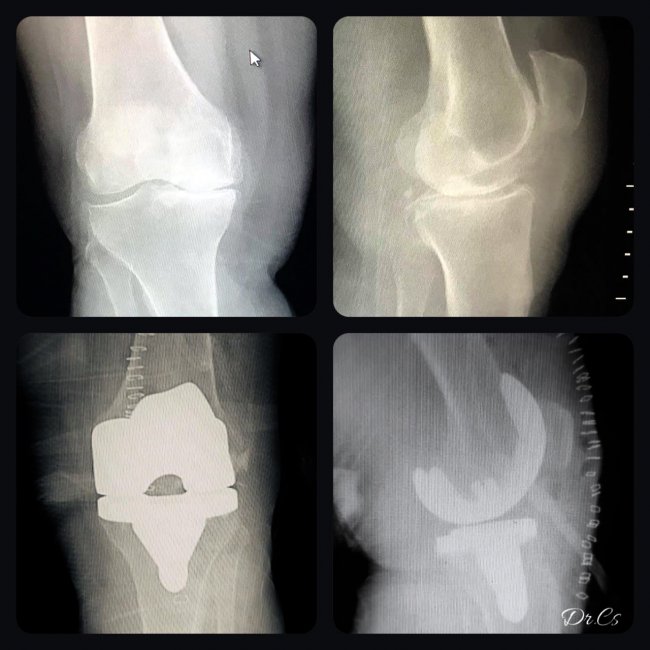

Türkiye'nin en önemli kış turizm merkezlerinden biri olan Cıbıltepe Kayak Merkezinde gelen yerli ve yabancı turistlere, olası ayak, kol, kalça gibi kırılma ve yaralanmalarda Ortopedi servisi anında müdahale ederek hastaların çok hızlı bir şekilde şifa bulmasını sağlıyor.

Son teknolojiyle büyük hastanelerde verilen hizmetler gibi hizmet verilmesi, hastaları da memnun ediyor. Özellikle kayak merkezinden gelen turistler Sarıkamış Devlet Hastanesi'nde tedavileri yapılıyor.

Hastanenin ortopedi uzmanı doktor Cihan Sevim, Sarıkamış kayak merkezinin ülkenin en önde gelen kayak merkezlerinden bir durumunda ve revaçta olmasıyla istenmeyen kazaları da beraberinde getirdiğini söyledi.

Sarıkamış Devlet Hastanesi olarak tüm hastalara hiçbir şekilde başka bir şehre gitmeden en hızlı sürede hizmet verdiklerini anlatan Sevim, "Kayak sezonunda genelde kaval kemiği ve el bileği kemiği çok görmekteyiz. Kayak mevsiminde son üç ayda 32 kırık ameliyatı, 180 kırığı alçı tedavisini gerçekleştirdik. Ayrıca 36 omuz, 7 dirsek çıkığını da kendi acil servisimizde yerleştirdik." dedi.

Sevim, hastalara hızlı ve en iyi hizmeti verdiklerini ifade ederek, "Ameliyathanemizde çok kompleks 10 kişilik ekibimiz var. Malzeme bakımından hastanemizin hiçbir eksiği yok. Hastalarımız hastanemize güvenle gelebilirler. Biz burada büyük hastanelerde verilen tüm hizmetleri kendimiz veriyoruz. Burada veremediğimiz hiçbir ortopedik hizmeti bulunmamaktadır. Kayak için gelen turistler mutlaka eğitmenlerden eğitim alarak kendilerini yeterli hissettikten sonra pistlere çıkmalarını öneriyorum. Burada çok kaliteli eğitmenlerimiz var, snowboard ve kayak dersi veriyorlar. Ders aldıktan sonra kendi başlarına kayak yapabilirler. Sarıkamış'ta kayak merkezi olduğu için burada ortopedi doktoru olarak çalışmak gerçekten yorucu oluyor. Ama hastaların memnuniyetini görünce ve kendi işimi sevdiğim için buda bizi mutlu ediyor." diye konuştu.